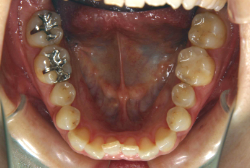

「ものがうまく噛めない」という主訴で来院したケースです。診断の結果、「骨格性反対咬合に伴う咬合不良+軽度叢生」と判明しました。原因としては特に下顎の左側が過成長したため、骨格性反対咬合になり、特に左側での噛み合わせが非常に悪くなっていると診断しました。初診時の写真を見ると、上下の正中線の大きなズレ、左側の噛み合わせの不良がはっきり分かります(黄色の矢印と緑の矢印は一致しているのが正しい状態です)。

そもそも、このような状態となっているのは骨の大きさに問題があるため生じていますので、場合によっては、「外科矯正」によって下顎の骨を外科的に縮めることで修正します。患者様が外科矯正をご希望されない場合は、従来ですと上下左右の小臼歯抜歯を行い矯正するのが普通です。

今回の患者様の場合は、「外科」も「小臼歯抜歯」も拒否されましたので、歯科矯正用アンカースクリュー(以下 アンカースクリュー)を用いて、下顎の歯列全体を後方に下げるという方法を取りました。

治療中の写真で、アンカースクリューより歯を後ろへ牽引しているのがお分かりいただけるかと思います。牽引を1年ほど続け、途中補助的に上下にゴムをかける(これを顎間ゴムと言います)手法なども追加し、全体で21ヶ月で治療を終えることが出来ました。

結局歯の本数を減らすことなく、すべてご自分の歯を残して、正しい配列と噛み合わせにすることができました。凸凹があまりひどくないため、簡単そうに見えると思いますが、このケースの初診の状態を見ると、熟練の矯正歯科医でも悩みのつきないケースです。まして、外科も出来ない、抜歯もイヤ、と言うことになると、従来の方法では治療不可能と考えられるのですが、アンカースクリューを使うことで最近は不可能が可能となってきました。